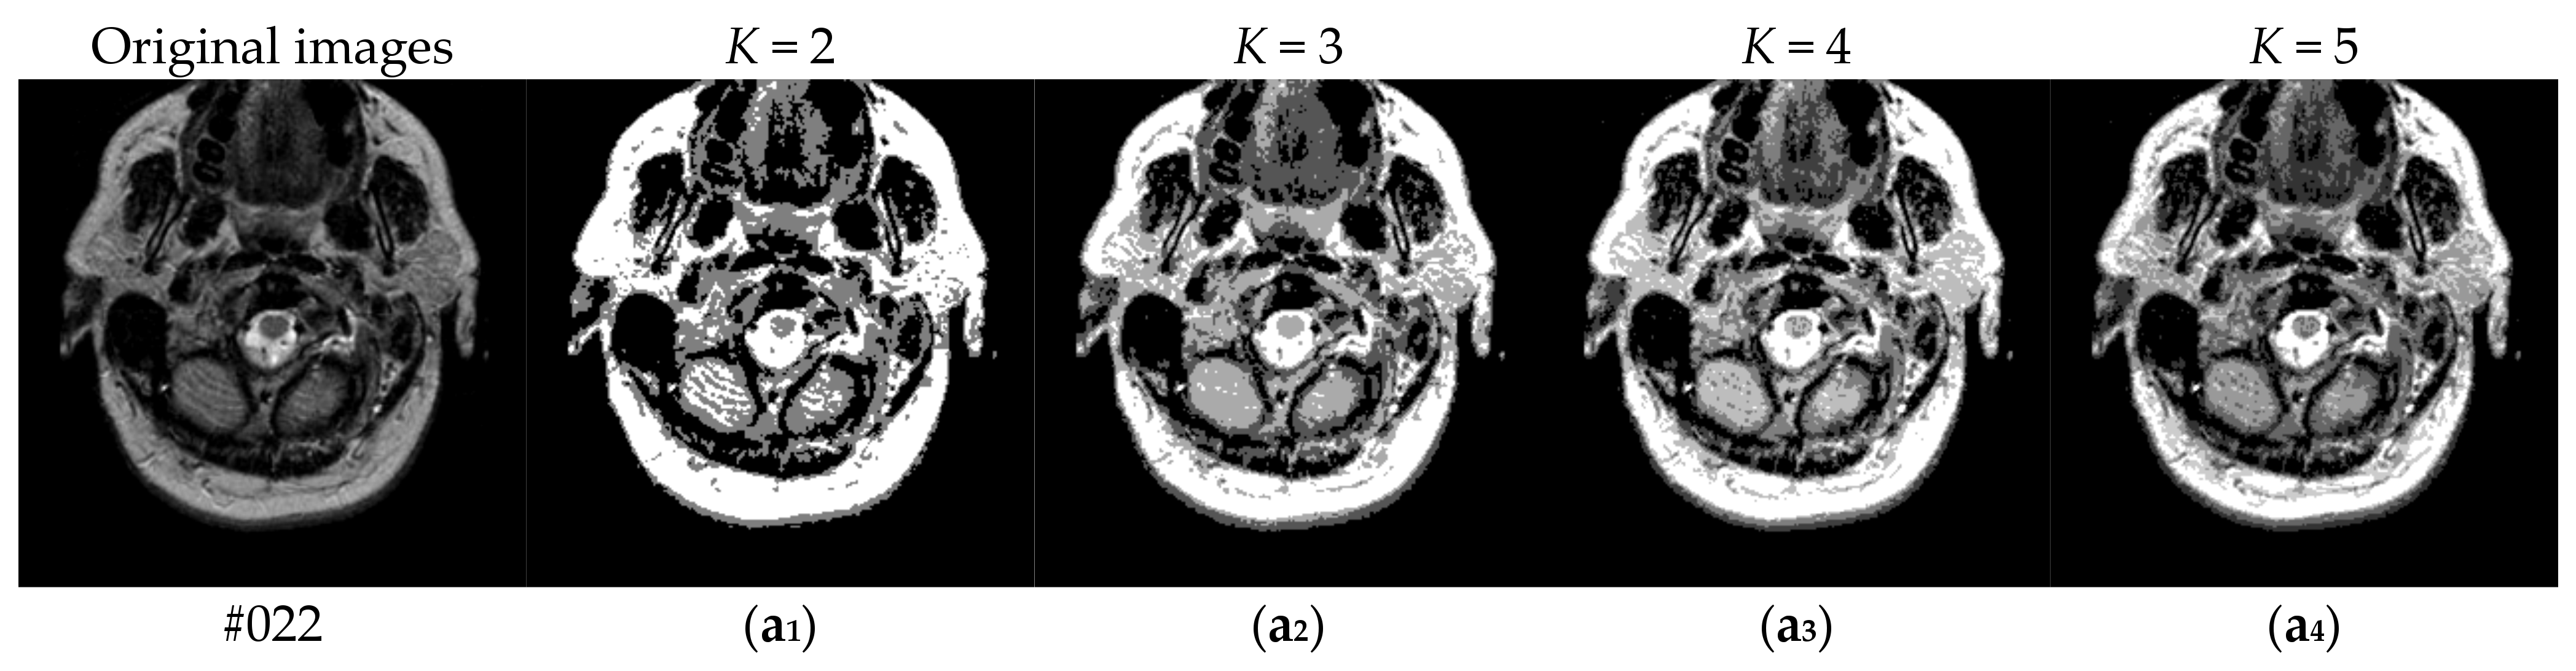

Figure 6 shows the results of two test images processed by the proposed hybrid spatial filter. It can be seen that the images after hybrid spatial filtering are smoother. The noise has been removed, and the details and structural information in original images are well preserved.

Figure 6.

An example of hybrid spatial filter. (a) Original images, (b) Part of the enlarged original images (c) The results obtained by hybrid spatial filter, (d) Part of the enlarged results images.